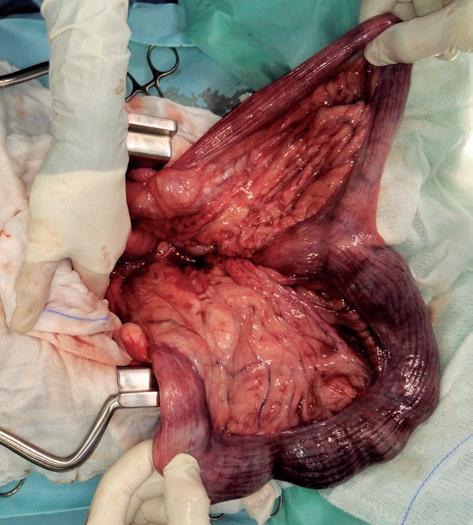

Complicaciones quirúrgicas en cirugía de urgencia (II): sistema genitourinario